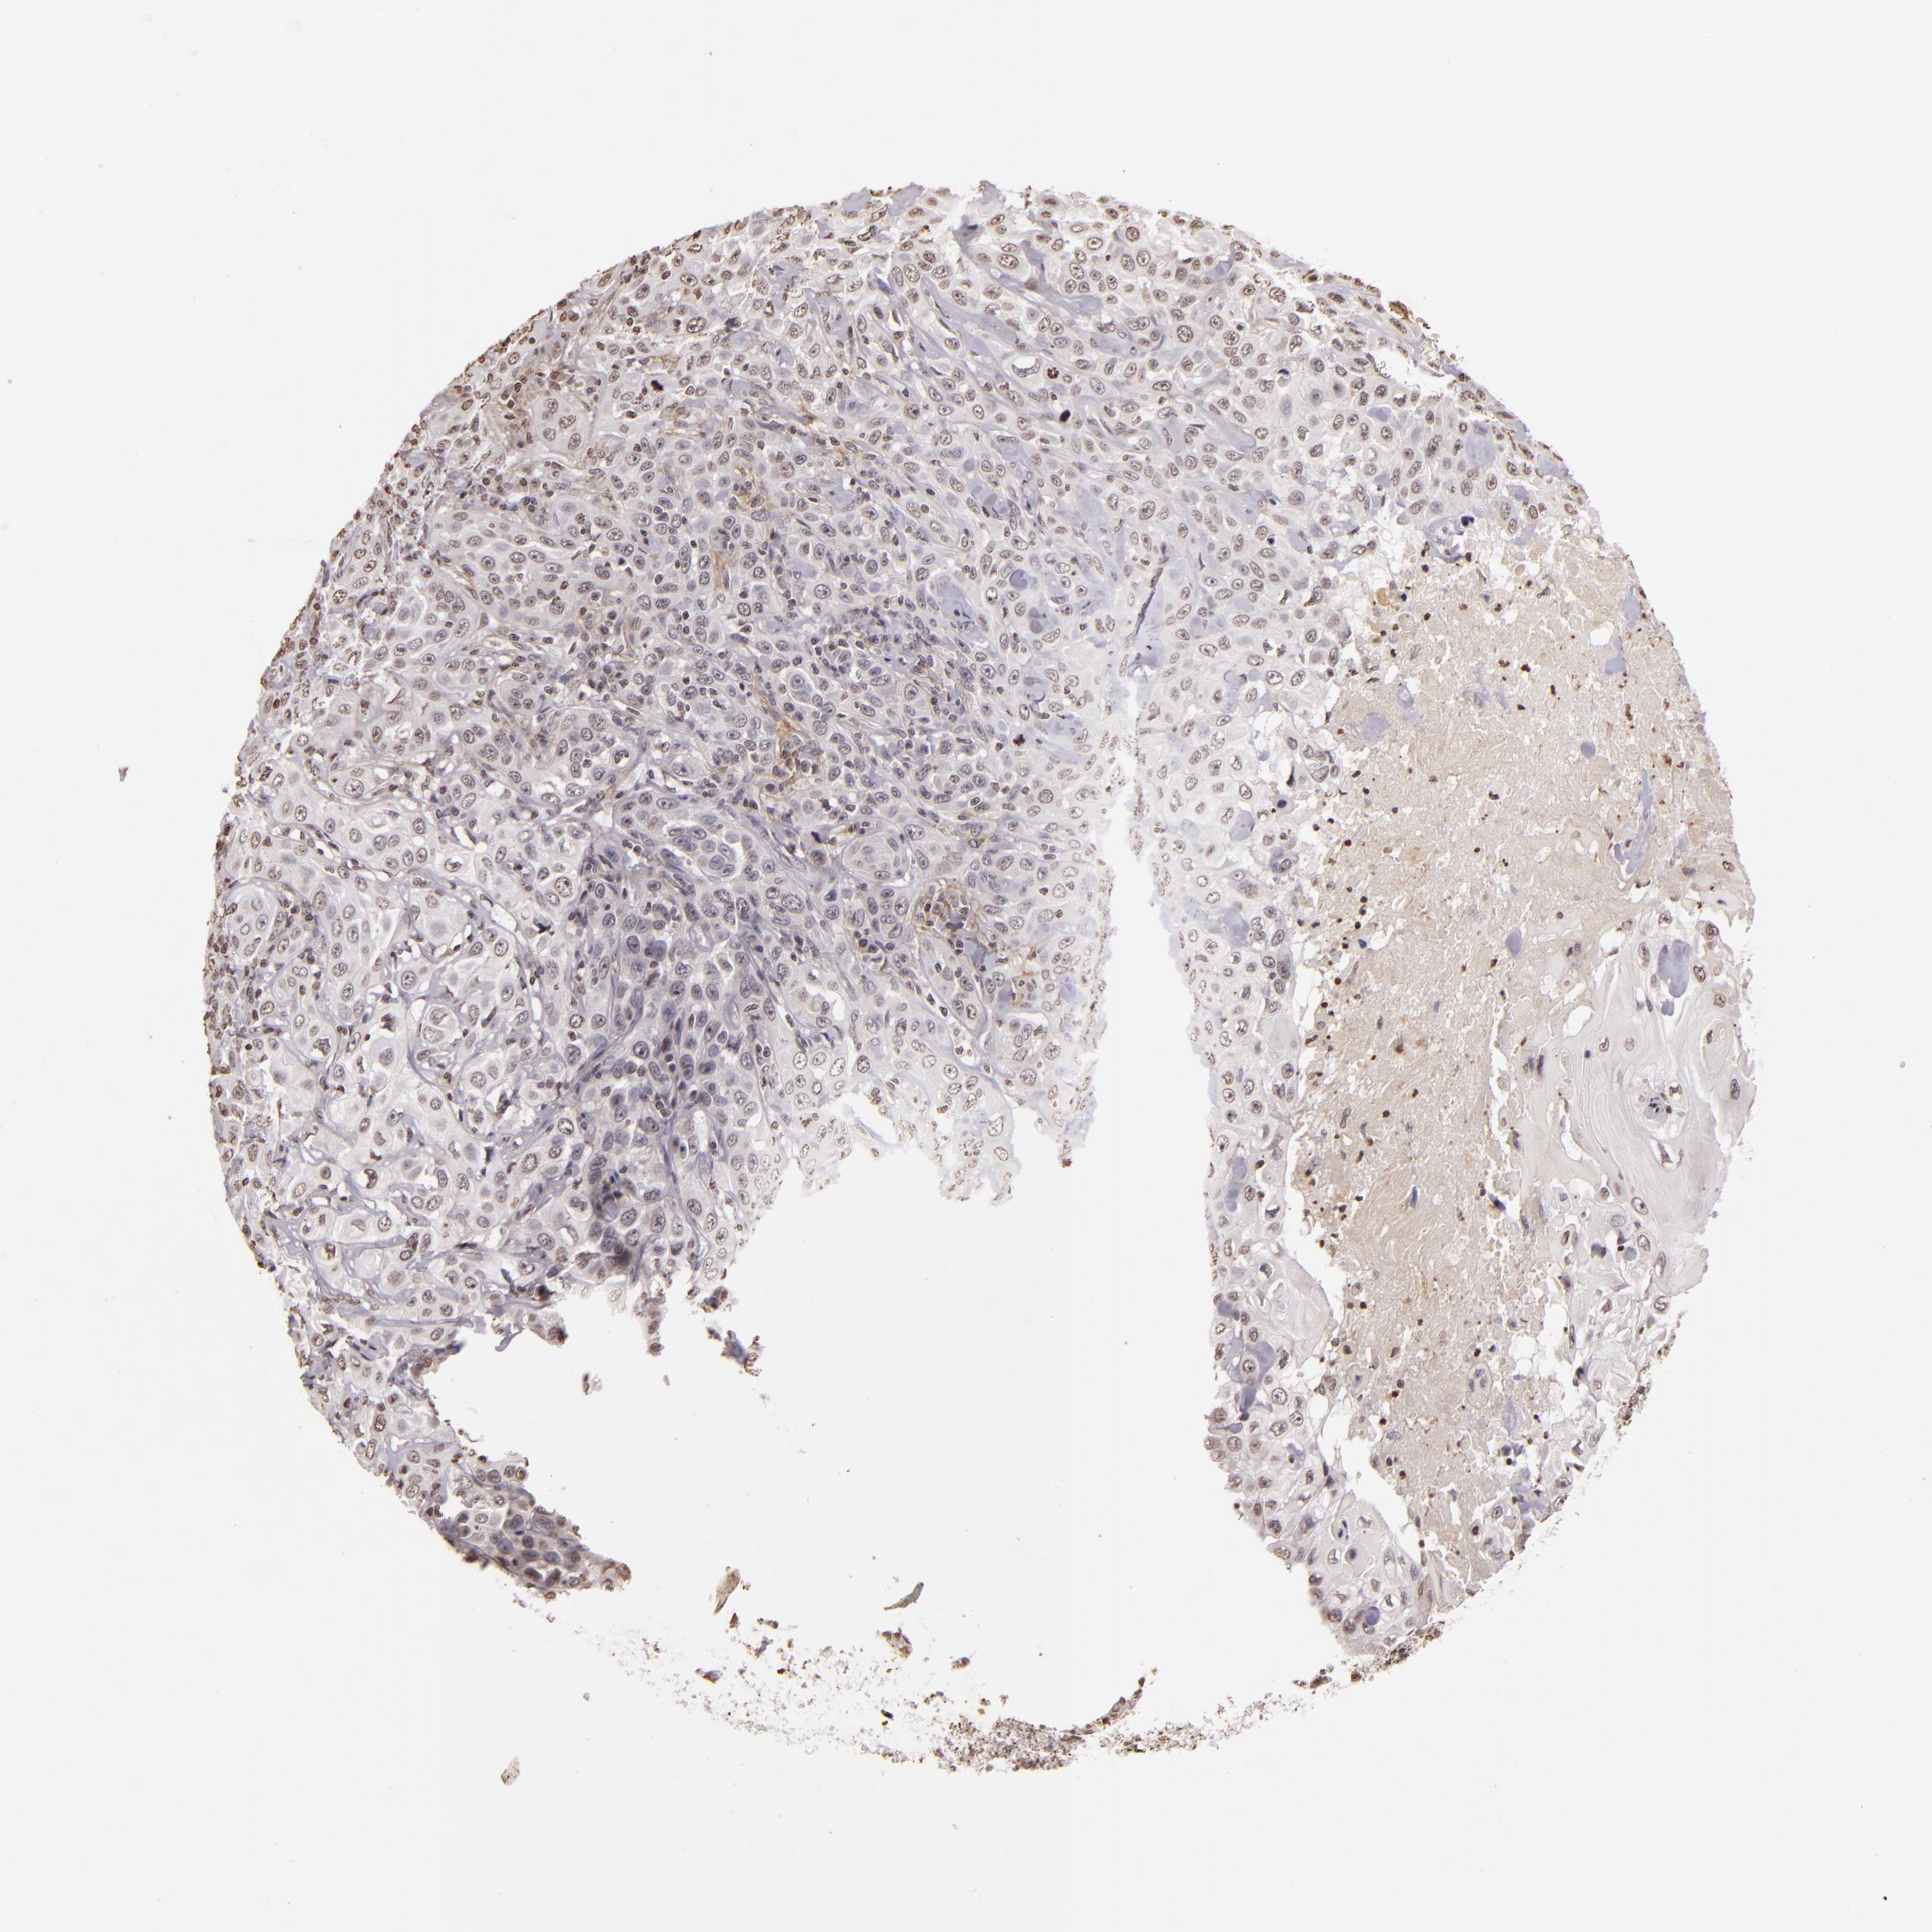

SKIN CANCER - Protein expressioni

A mouse-over function shows sample information and annotation data. Click on an image to view it in a full screen mode. Samples can be filtered based on level of antibody staining by selecting one or several of the following categories: high, medium, low and not detected. The assay and annotation is described here.

Note that samples used for immunohistochemistry by the Human Protein Atlas do not correspond to samples in the TCGA dataset.

Antibody staining in the annotated cell types in the current human tissue is reported as not detected, low, medium, or high, based on conventional immunohistochemistry profiling in selected tissues. This score is based on the combination of the staining intensity and fraction of stained cells.

Each image is clickable and will lead to virtual microscopy that enables deeper exploration of all samples and also displays staining intensity scores, fraction scores and subcellular localization as well as patient and tissue information for each sample.

Antibody CAB002008

Squamous cell carcinoma, NOS